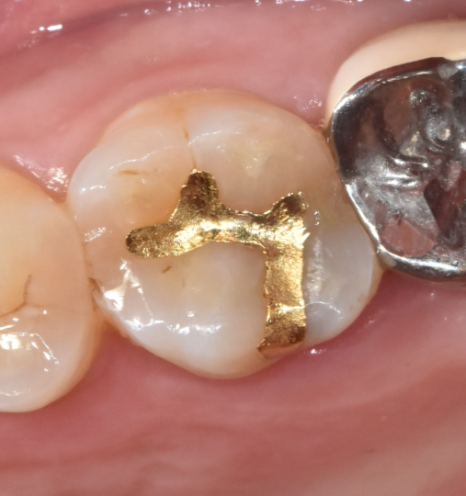

- 충치가 넓고 깊다면? – 인레이와 온레이

충치가 깊거나 크기가 커진 경우에는 레진으로는 부족할 수 있습니다.

이럴 때 사용되는 치료가 바로 인레이와 온레이입니다.

떼우는 형태에 따라 이름이 달라지는 것일뿐

같은 치료인데요~

241028

앞에서 보았던 레진 치료 시 보았던 구멍보다

범위가 넓죠!?

충치가 넓게 퍼져있거나 (가로로)

수직으로 깊게 있지만 신경은 뚫리지 않았을 때 (세로)

시행하고 있습니다.